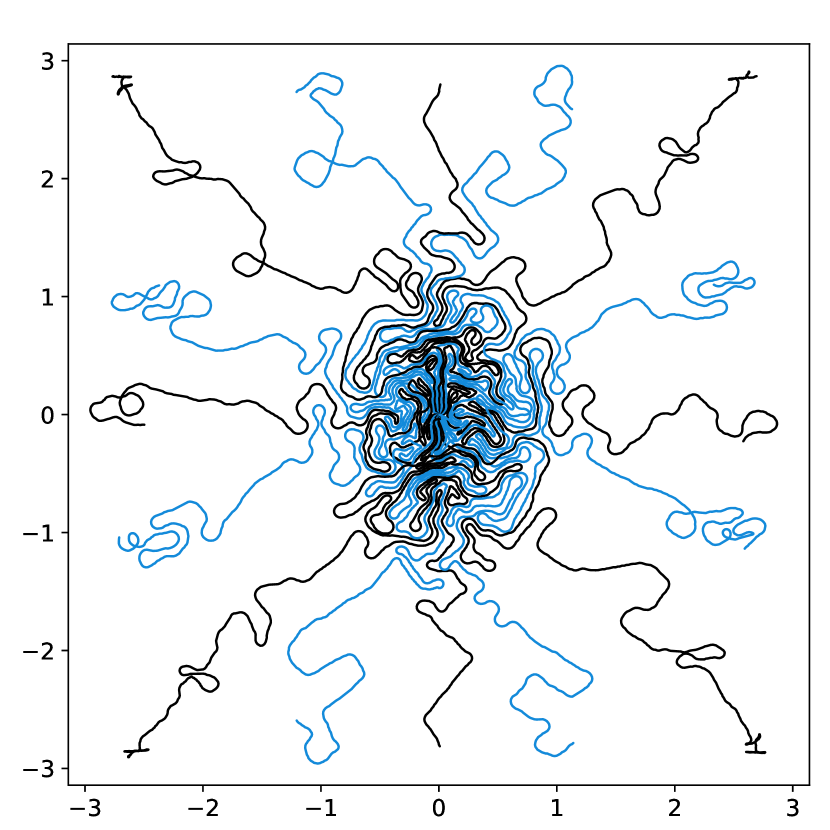

A natural approach to solve (6) is to optimize the coefficients using a gradient based algorithm. Indeed, one may hope that the reparameterization of the cost function with a density prevents the appearance of spurious minimizers described in Gossard et al. (2022). Unfortunately, this is not the case and gradient based algorithms might be trapped in such local minimizers. Fig. 4 and 5 illustrate this fact. In Fig. 4, the baseline sampling scheme is shifted continuously in the and directions. The cost function is evaluated for each shift and displayed in the right. Observe that many local minimizers are present. Similarly, in Fig. 5, a target density is varied continuously in a subspace consisting of eigen-elements . Again, the energy profiles on the right are highly oscillatory.

Overall, this experiment shows that the gradient direction is not meaningful: it oscillates in an erratic way. This advocates for the use of 0th order optimization methods. A significant advantage of this observation is that it allows discarding the memory and time issues related to automatic differentiation.

images.

images.